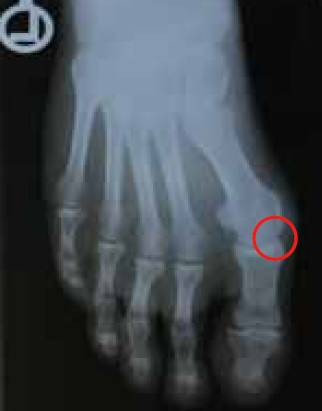

1.拇指外翻

正常拇指向外的角度需小于15度,超过即为拇指外翻。常合并趾关节滑囊炎,会反复发炎且非常疼痛。若是治疗必定持续恶化。需使用鞋垫改善整个足部力学的状态。